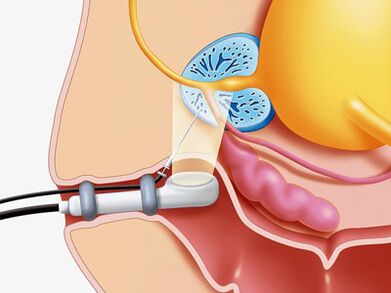

- Ein Komplex von Instrumentalmethoden (Ultraschall).

Ultraschallstudie

Im Falle eines Verdachts einer Prostatakrankheit wird eine Ultraschalluntersuchung der Drüse selbst verwendet (transiental Ultraschall), Nieren und Blasen optimal, sodass Sie feststellen können:

- Volumen und Abmessungen der Drüse.

- Das Vorhandensein von Kalkül.

- Die Abmessungen der Samenblasen.

- Der Zustand der Wände der Blase.

- Die Menge an Resturin.

- Kleidungsstrukturen.

- Eine andere Art von Pathologie.